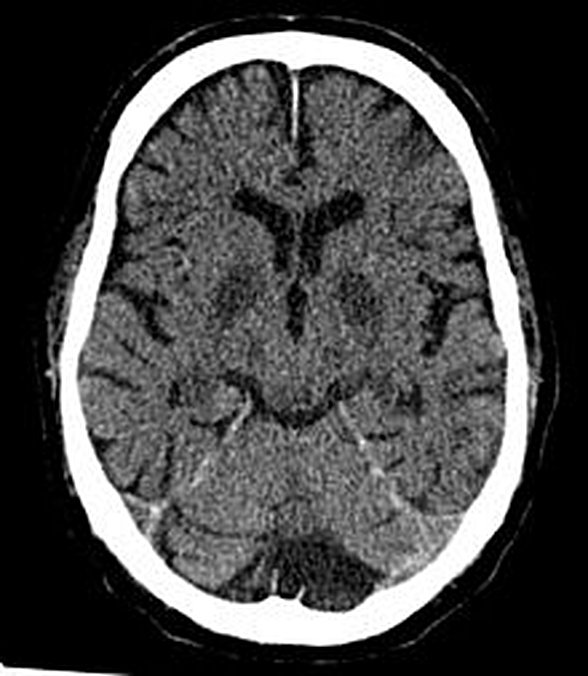

Olarak sınırlanabilir bir diğer ve şu an için en kesin bakılan iddia ise şudur kalbin durması sebebiyle bir süre sonra beynin oksijensiz kalması ve Serebral hipoksi (Cerebral hypoxia) olarak adlandırılan tabloya neden olarak beynin normal çalışma ritminin bozulması sonucu halisünasyonların ve vizyonların görülmesidir lakin dediğimiz gibi kesin bir tetikleyici olduğunu söylemek yanlış olacaktır haliyle buna bile temkinli yaklaşırken olayı mistik fenomenlere bağlamak yanlış olacaktır.